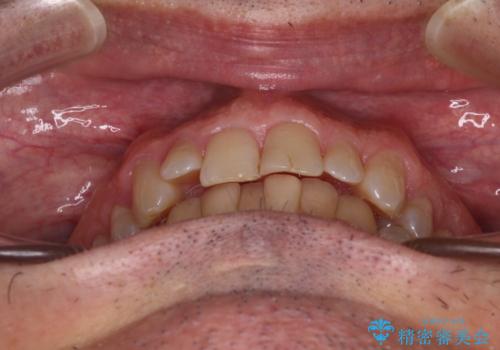

【モニター】前歯のデコボコを治したい インビザライン矯正治療

- 前歯のデコボコを気にして来院された患者様です。

インビザラインでもワイヤー装置でも対応可能でしたが、仕事の都合で来院回数を減らしたいとのことでインビザラインによる矯正治療を選択されました。

著しく咬合力が強いため、奥歯がしっかりと噛めずに治療が長引くことが懸念されました。

1セット目のインビザラインを使用した際には左右ともに大臼歯が咬み合っていなかったのですが、2セット目できっちりと仕上げることができました。